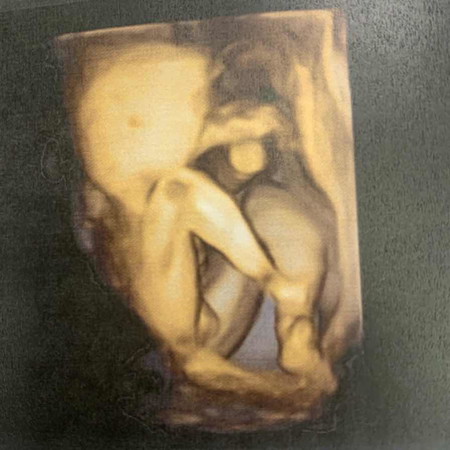

ช่วยดูเพศน้องหน่อยค้า

น้องเพศอะไรค้าาา า 🥰

เหมือนจะเป็น ผช.เลยค่ะ ให้สามีดูนางบอก ผช.สิแบบนี้(ประนึ่งเป็นคุณหมอ)😊

คิดว่าผู้ชายนะคะ ถ้าผู้หญิงของน้องจะเห็นเป็นกลีบ2อัน

คิดว่าหญิงค่ะเพราะถ้าผู้ชายจะมีหำชี้ขึ้นมาจ้า

ผุ้ชายค่ะนั่นใข่น้อง😅

หญิงมั้ยคะ บ้านนี้มองเป็น ญ คล้ายกลีบ

น่าจะผู้ชายนะคะ มีไข่น้อยๆ รอลุ้นต่อคะ

น่าจะผู้ชายค่ะ เหมือนเห็นถุงอัณฑะ

ผู้ชายค่ะ!โชว์ไข่เลยนะลูก😄😄

น่าจะผู้ชายค่ะ เห็นไข่น้อง

เหมือนมีไข่นะ ชายมั่งค่ะ